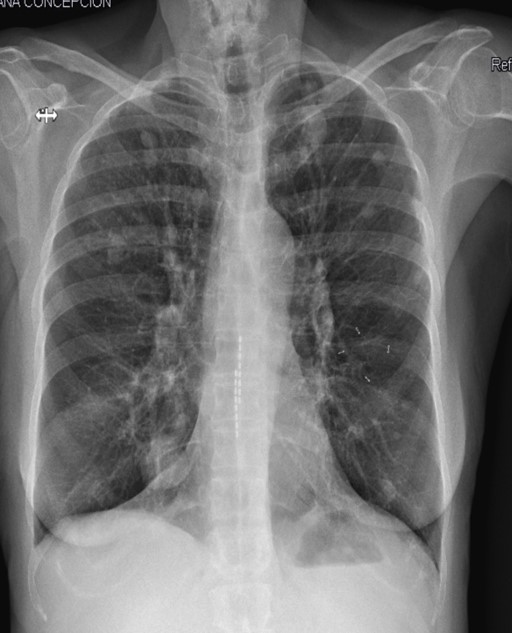

- Radiografía de tórax: Imágenes compatibles con posibles metástasis pulmonares («suelta de globos»).

- TAC toracoabdominal: Masa sólida de gran tamaño en región hepatorrenal, posiblemente de origen suprarrenal, acompañada de múltiples metástasis pulmonares.